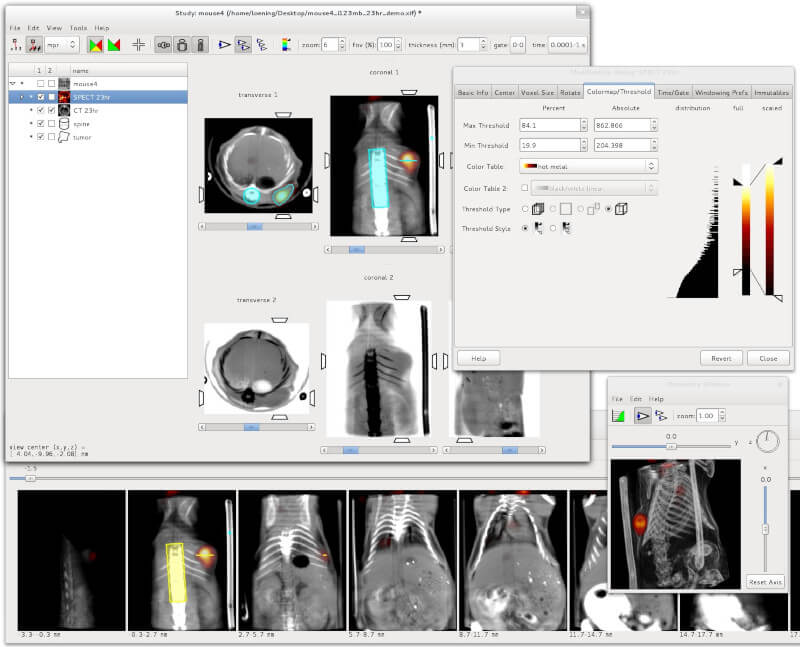

1. Amide

Amide is a cross-platform GTK+ tool for viewing, registering, and analyzing volumetric medical imaging data sets.

It uses a GUI with a long feature list including loading multiple data sets at once, generating fly through movies as MPEG1 files, an anisotropic filtering wizard, thresholding datasets independently and in bulk, etc.